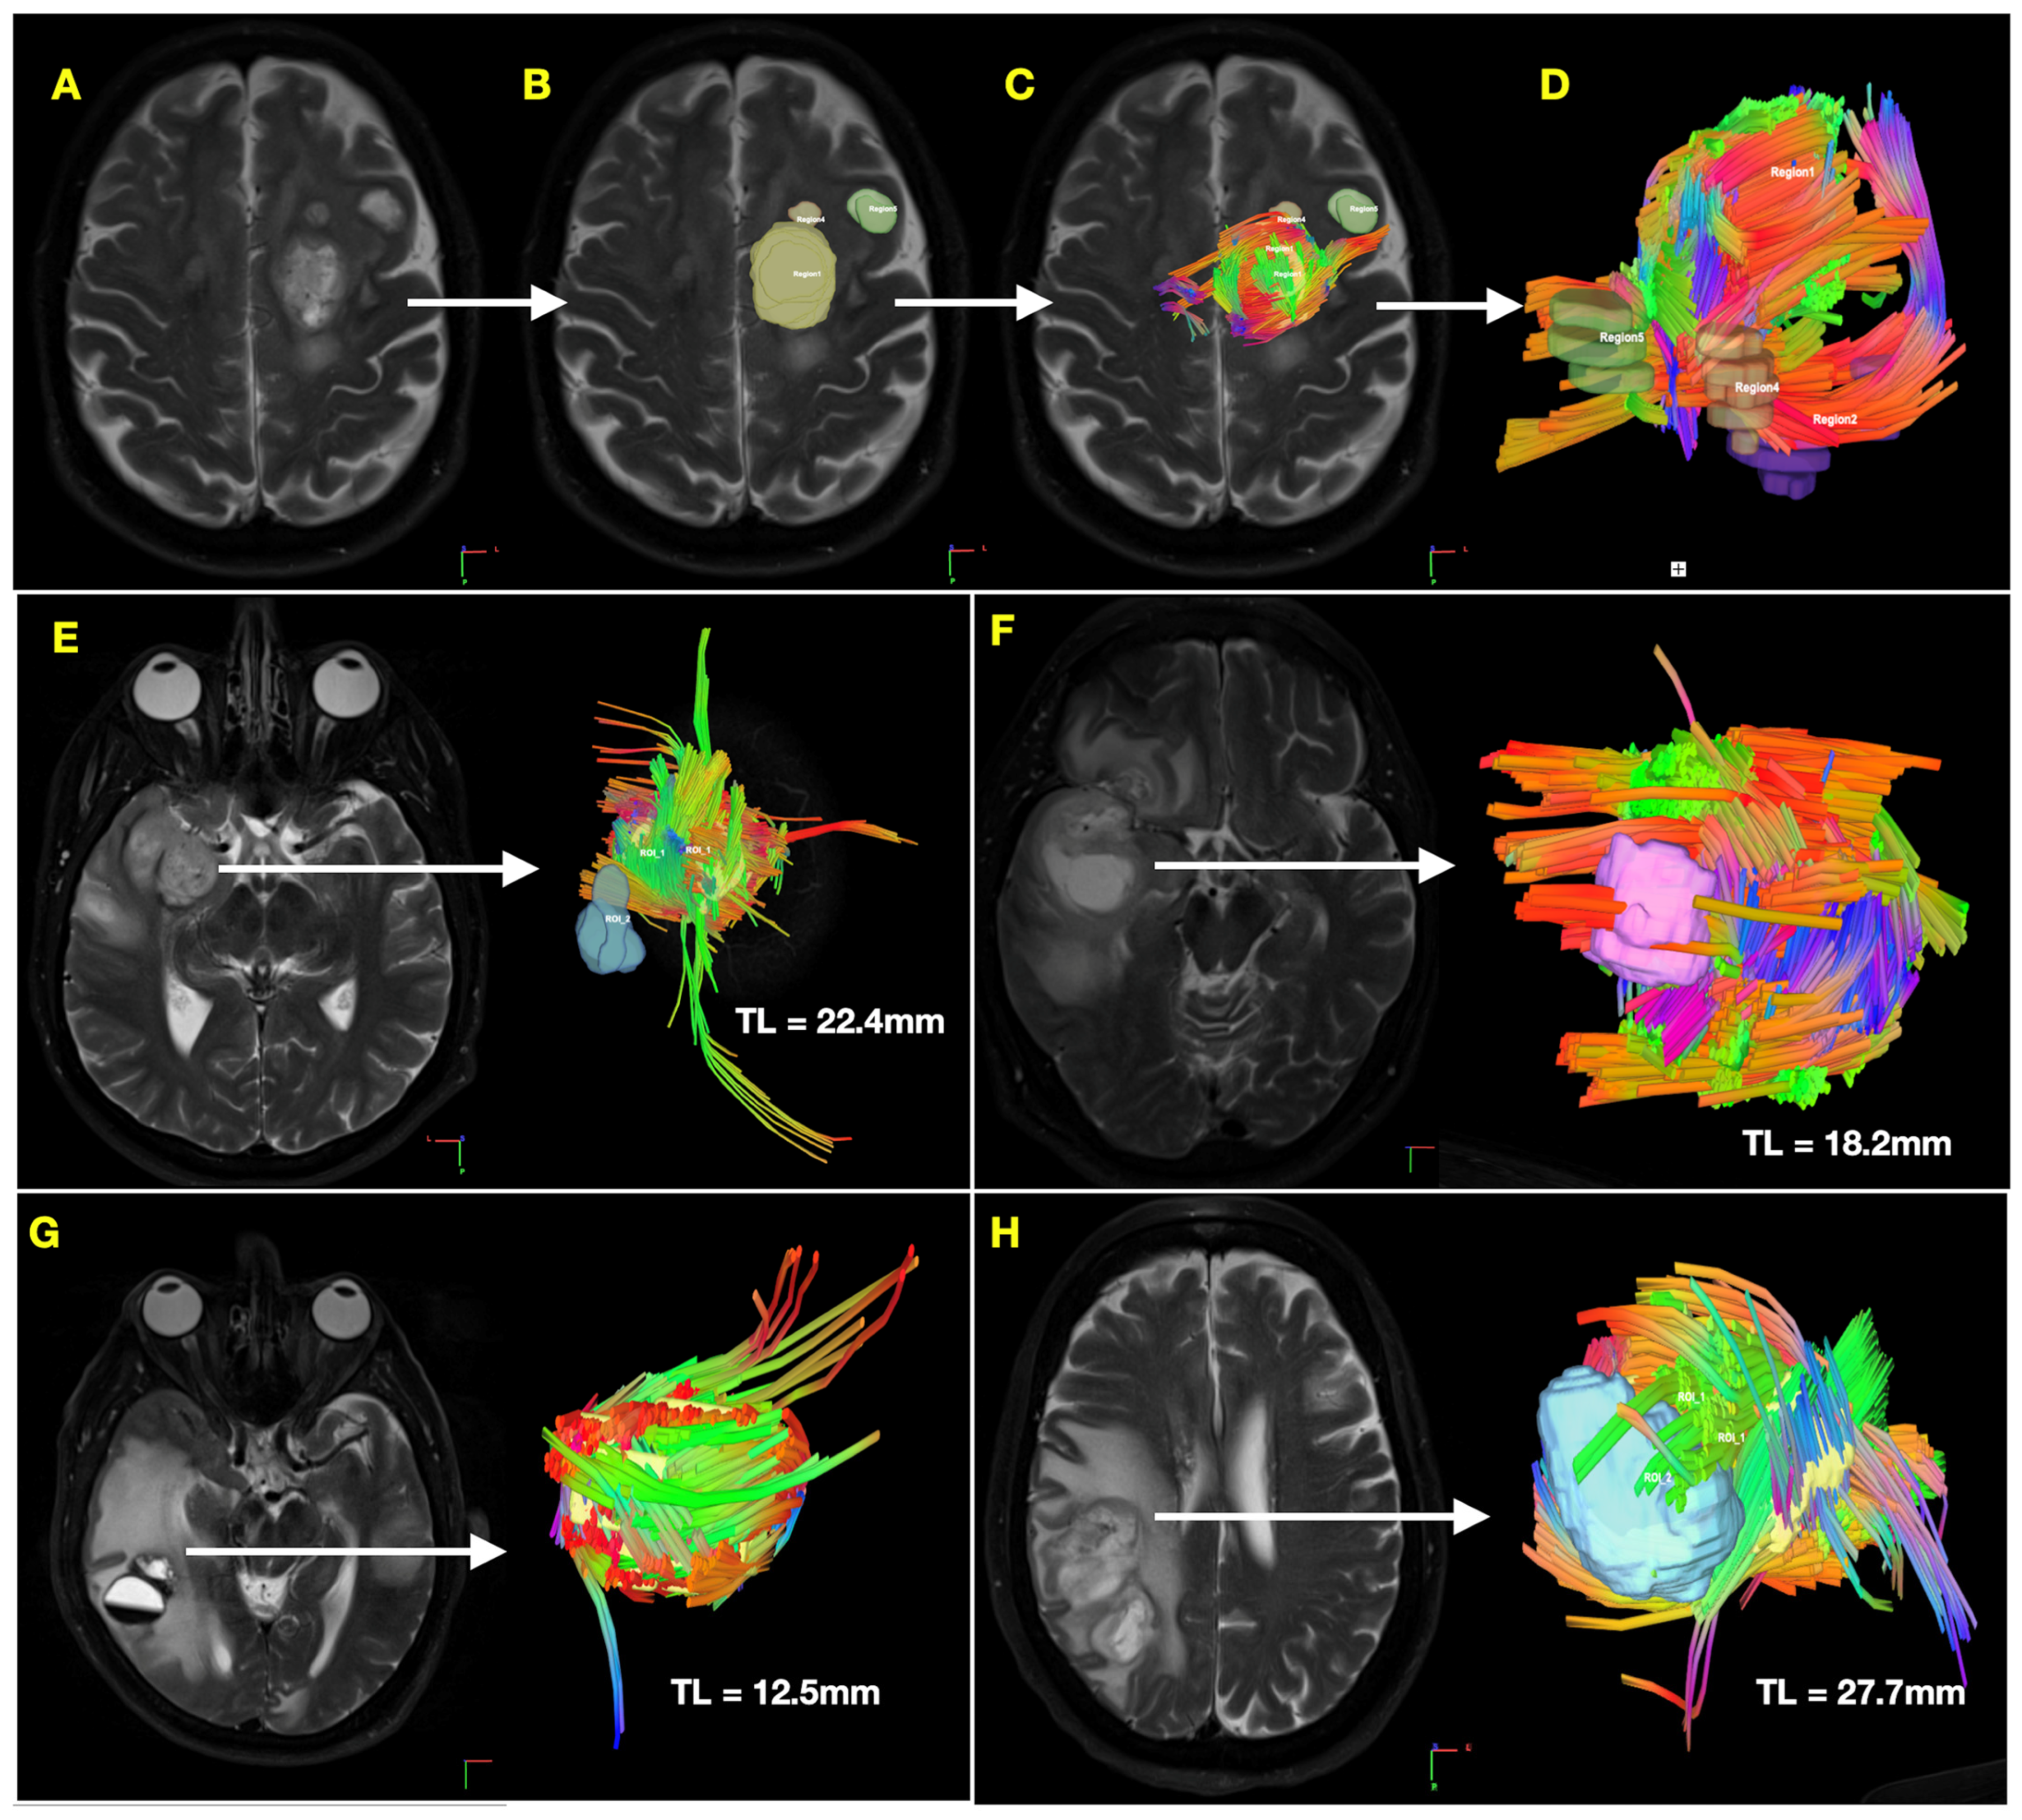

| Generalized Q-Space Imaging (QSI)-Derived Tractography Features | |

| Mean Tract Length (mm) | 23.2 (±3.1) |

| Mean Projecting Tract Length (mm) | 38.9 (±4.9) |

| Mean Tract Length (mm) | 29.1 (±11.7) | −7.79 (−21.88, 6.31) | 0.274 |